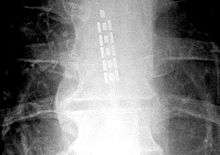

![]() Anterior view X-ray of a spinal cord stimulator (SCS) implanted in the thoracic spine |

A spinal cord stimulator is a device used to exert pulsed electrical signals to the spinal cord to control chronic pain. Further applications are in motor disorders. The lumbar spinal cord is a preferred target for the control of spinal spasticity[1][2] or augmentation of standing and stepping capabilities.[3][4][5][6] Spinal cord stimulation (SCS), in the simplest form, consists of stimulating electrodes, implanted in the epidural space, an electrical pulse generator, implanted in the lower abdominal area or gluteal region, conducting wires connecting the electrodes to the generator, and the generator remote control. SCS has notable analgesic properties and, at the present, is used mostly in the treatment of failed back surgery syndrome, complex regional pain syndrome and refractory pain due to ischemia.